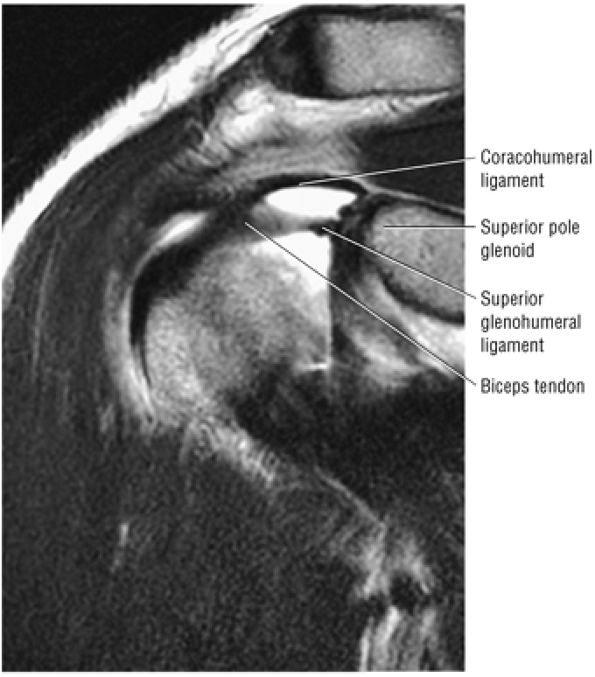

The superior glenohumeral and coracohumeral ligaments stabilize the long head of the biceps tendon by forming the biceps pulley or sling in the rotator cuff interval.

of the humeral head. Warner et al. showed that the SGHL was well developed in 50% of shoulders.69 When present and well formed (developed), the SGHL represents the primary capsuloligamentous restraint to inferior translation of the unloaded, abducted shoulder joint.59,69 Both the SGHL and the CHL have an important role in forming the biceps pulley of the rotator cuff interval.